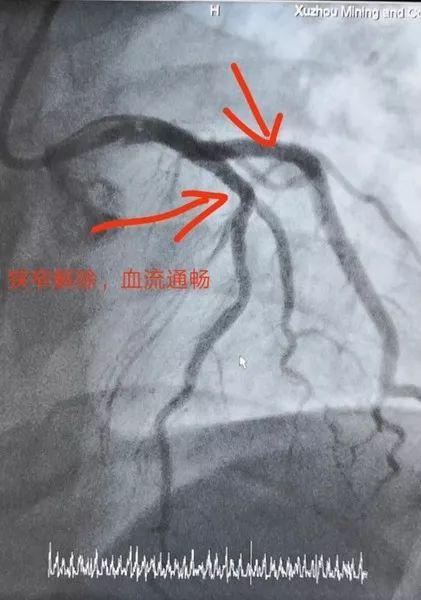

经过急查心肌酶谱明确急性心肌梗死的诊断,同时急诊的冠脉造影检查显示,这名年轻患者的前降支堵塞程度达到99%,血流缓慢,回旋支狭窄90%,立即给予介入支架术,术后患者症状消失。因为患者来医院较为及时,在接受了介入手术植入支架以后,病情很快缓解。

比如,上文中31岁的这位患者,从急诊到介入手术球囊扩张顺利完成,用时40分钟。